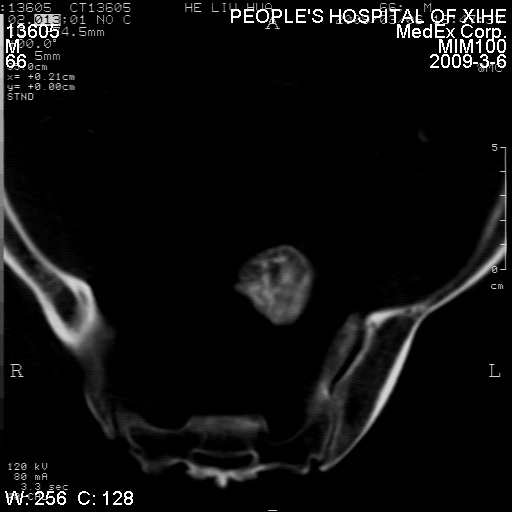

标题: CT18522:男,66岁。考虑结核有错吗 [打印本页]

标题: CT18522:男,66岁。考虑结核有错吗

x线片示:骶骨密度增高。

考虑----腰椎骶化-----退变-----椎管狭窄

腰骶椎退行性改变。

退行性变,椎体滑脱

腰椎滑脱并有退变

退行性变,椎体滑脱。建议同椎体平行进一步扫描。